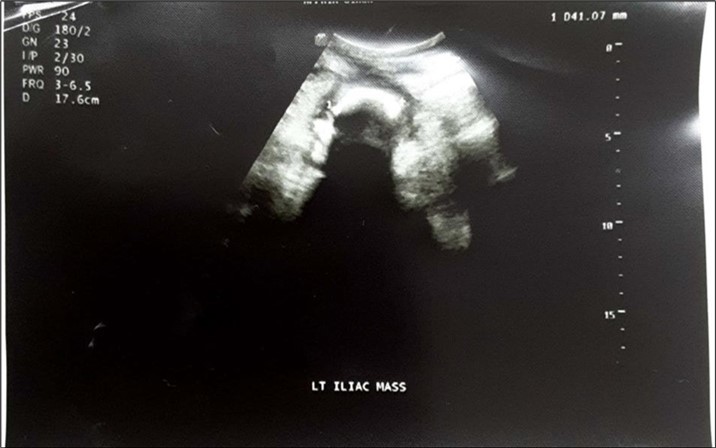

An impression of an intestinal obstruction due to postoperative adhesions was made. An abdominal X-ray done showed no obvious signs of bowel dilatation but an ill-defined opacification in the area of the left lumbar region (Figure 1). An ultrasonography done showed an echogenic mass in the left iliac region measuring about 4.1cm in diameter. There was no flow on colour doppler interrogation (Figure 2). At this point a diagnosis of foreign body was queried. The patient was counselled and prepared for exploratory laparotomy.

Figure 2.Abdominopelvic USG: An echogenic mass in the left iliac region measuring about 4.1cm in diameter. There was no flow on colour doppler interrogation.